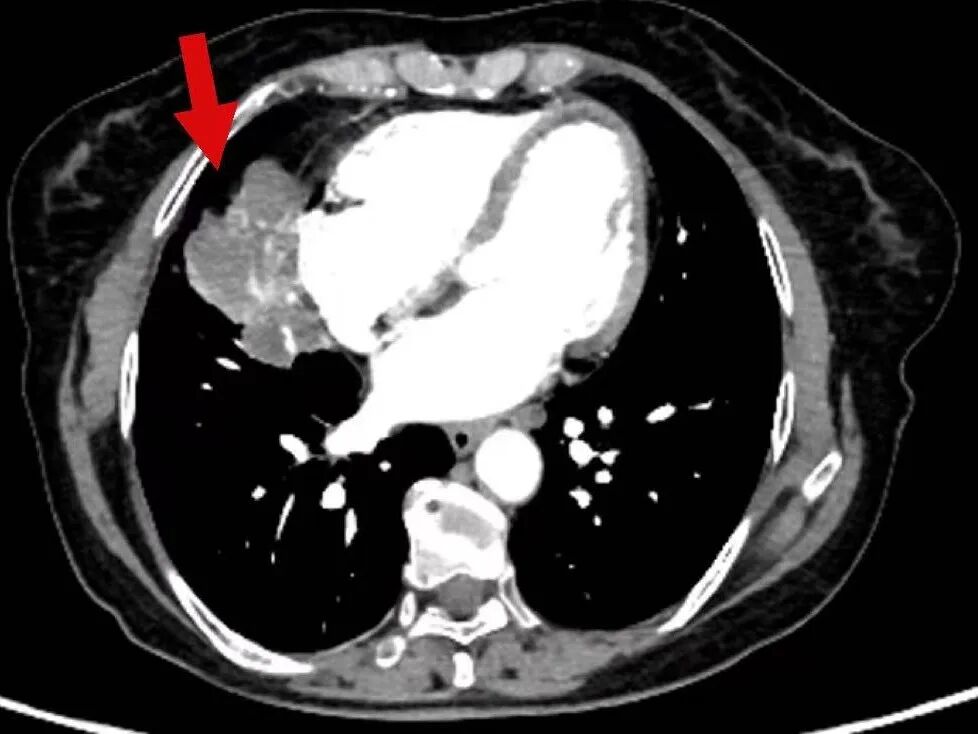

2025年3月17日,肿瘤诊疗中心团队首次为毕女士成功实施BACE治疗。术后患者病情暂时稳定,但5月10日复查显示肺部原发病灶稳定,肝脏转移病灶再次增大。

面对病情反复,团队没有放弃,果断升级治疗方案,决定同期施行BACE联合肝动脉化疗栓塞术,继续强化局部控制。“对于这类晚期患者,局部介入的优势在于能够高效、低毒地控制关键病灶。”介入医学科主任杨亚平说,“BACE联合肝动脉栓塞这类技术既能提高肿瘤部位的药物浓度,又减少了全身副作用,为后续治疗创造了条件。”

在玉溪市中山医院肿瘤诊疗中心治疗后,肿瘤在明显缩小